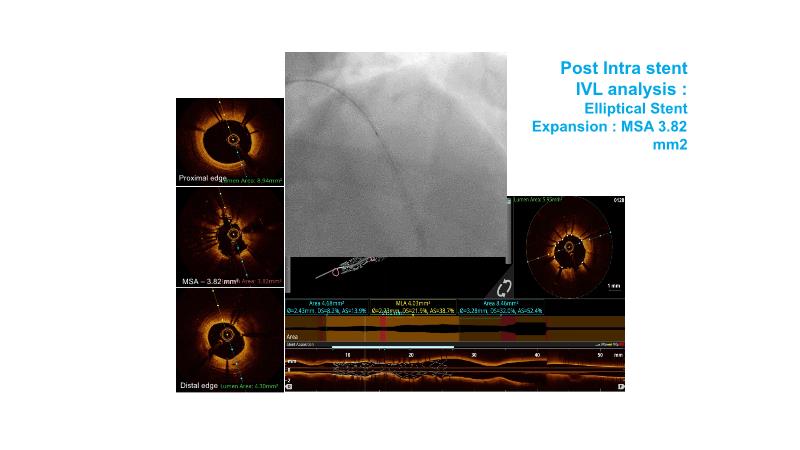

Revolutionising coronary calcium treatment: unleashing the potential of intravascular lithotripsy

Over the last five years, we have learned that there is a new tool for treating calcium, the greatest enemy of interventional cardiology, which can take various forms: intravascular lithotripsy. In this session, look at how to master this technique in different scenarios, from eccentric calcified lesions to left main bifurcations.

- To understand the mechanism of action of intravascular lithotripsy (IVL) for the treatment of calcified lesions